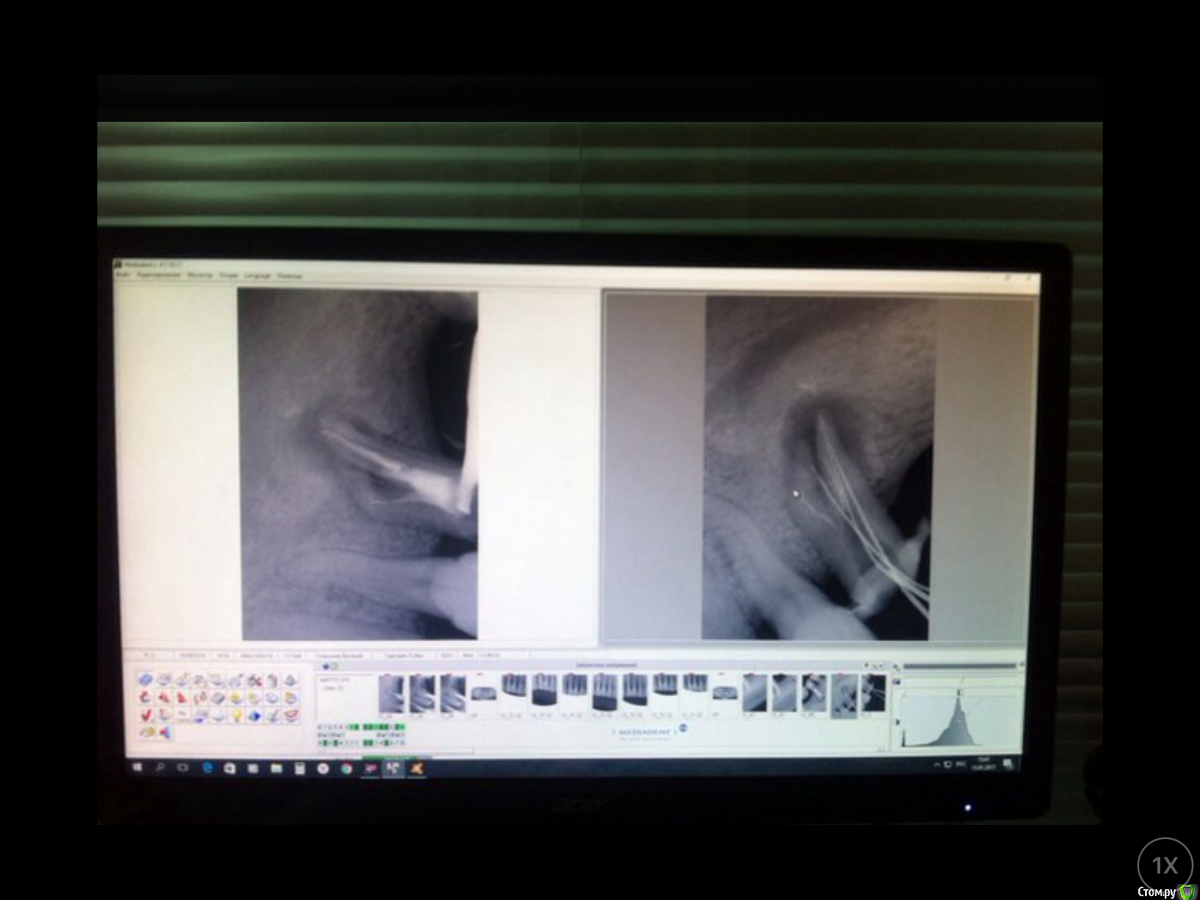

Гарриевич Опубликовано 10 февраля, 2017 Поделиться Опубликовано 10 февраля, 2017 Срезы КТ через 4 и 16 месяцевЭндодонтия не первичная, до этого пациента уже пытались лечить 15 Ссылка на комментарий

Гарриевич Опубликовано 2 августа, 2018 Автор Поделиться Опубликовано 2 августа, 2018 Новые данные есть http://images.vfl.ru/ii/1533249776/6f923f10/22735709_m.jpg 3 Ссылка на комментарий